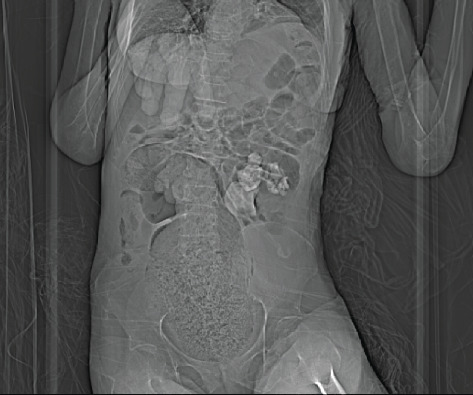

Background: Staghorn calculi are large renal stones which occupy most of the renal pelvis and are commonly associated with chronic or recurrent upper urinary tract infections (rUTIs). They often require more aggressive management, such as percutaneous nephrolithotomy (PCNL) or nephrectomy, although conservative management may be a safer option for select patients, particularly those with significant comorbidities. The presence of chronic stones or recurrent infections in the kidney increases the risk of complications, including fistula and abscess formation. Case Presentation: A 68-year-old female presented to the emergency department with signs of urosepsis. Computed tomography (CT) imaging revealed a left-sided staghorn calculus with concurrent smaller renal calculi. Due to worsening kidney function during hospitalization, repeat imaging was done, which revealed a staghorn calculus in the rectum. The staghorn calculus migrated to the colon through a renocolic fistula, and the patient subsequently passed the large staghorn through the rectum spontaneously. Conservative management was pursued due to her high surgical risk. Several months after discharge, she represented with signs of infection, and a large left-sided psoas abscess was identified. Conclusion: As the patient had severe comorbidities, our options to manage the staghorn calculi were very limited. She responded well to conservative management initially, but then was found to have another complication associated with the staghorn. It is acceptable to manage uncomplicated staghorn calculi conservatively in a small selection of patients, who are not good candidates for more invasive procedures, though in healthier and younger people, aggressive management is recommended to prevent further complications or deterioration. It is crucial to highlight the importance of early recognition and individualized treatment for renocolic fistulas, as timely intervention can significantly improve patient outcomes.